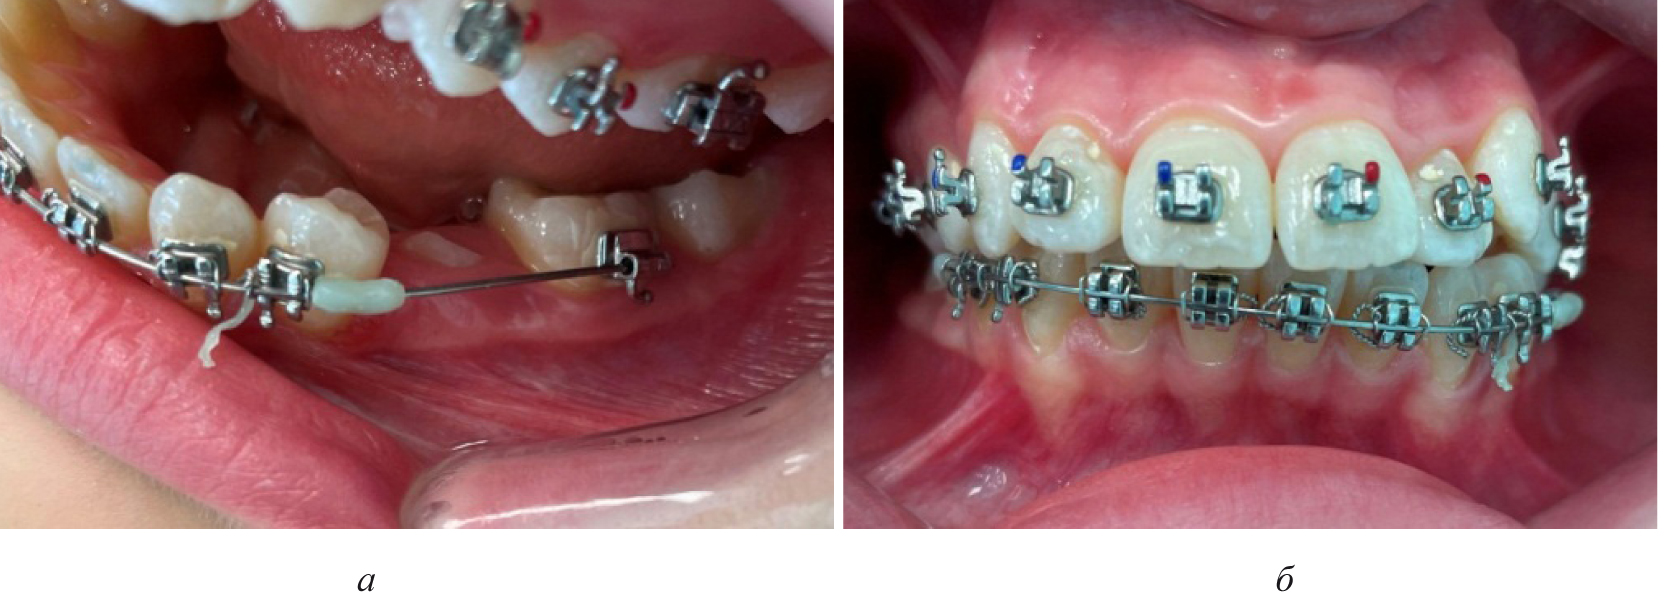

Лечение пациентов, как правило, проводилось с использованием несъемной ортодонтической аппаратуры, в частности эджуайс-механикой.

На первом этапе проводилось раскрытие пространства в области ретенированного зуба и создания условий для его прорезывания. После этого устанавливались элементы аппарата на противоположной челюсти (рис. 4).

Рис. 4. Создано место для прорезывания премоляра (а), установлена аппаратура на верхнюю челюсть (б)